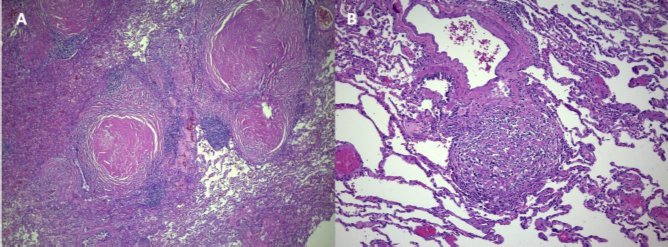

The histopathological examination revealed non-necrotizing granulomatous inflammation with areas of hyalinization, findings consistent with sarcoidosis. Stains for bacilli and fungi, including Kinyoun, GMS, and PAS, were negative, excluding the possibility of tuberculosis or any other infectious process (Fig. 3). Polarized light microscopy identified a small quantity of material consistent with silica, insufficient to corroborate the diagnosis of silicosis associated with systemic sclerosis.

(A) Lymphangitic distribution nodules with extensive hyalinization surrounded by lymphoid aggregates, HE; 4X. (B) Hyalinized nodule with fibroblasts and histiocytes, HE; 20X.